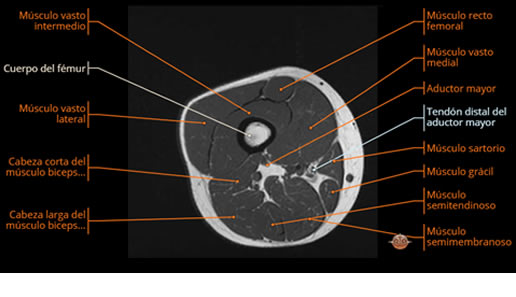

Se realiza estudio de MRI de muslo izquierdo en diferentes planos, con secuencias de Spin Echo, GRE; ponderadas a T1 y a T2, se utilizan pulsos de saturación de grasa y se administra medio de contraste IV a base de Gadolinio en base al peso del paciente.

La diáfisis femoral izquierda muestra reacción perióstica importante, se extiende desde el cuello del fémur, invade trocánteres, diáfisis femoral, medial y distal, es compatible con un proceso infeccioso óseo, el complejo muscular del muslo se ve edematizado.

La resonancia es la modalidad de elección para valorar la extensión intramedular y la infiltración en tejidos blandos, brindando una imagen más detallada del compromiso tumoral. Los hallazgos característicos incluyen:

Lesión de señal heterogénea en secuencias T1 (hipointensa) y T2/STIR (hiperintensa), que refleja necrosis, hemorragia y contenido celular diverso.

Compromiso de la médula ósea adyacente y de estructuras vecinas, como músculos y neurovasculatura.